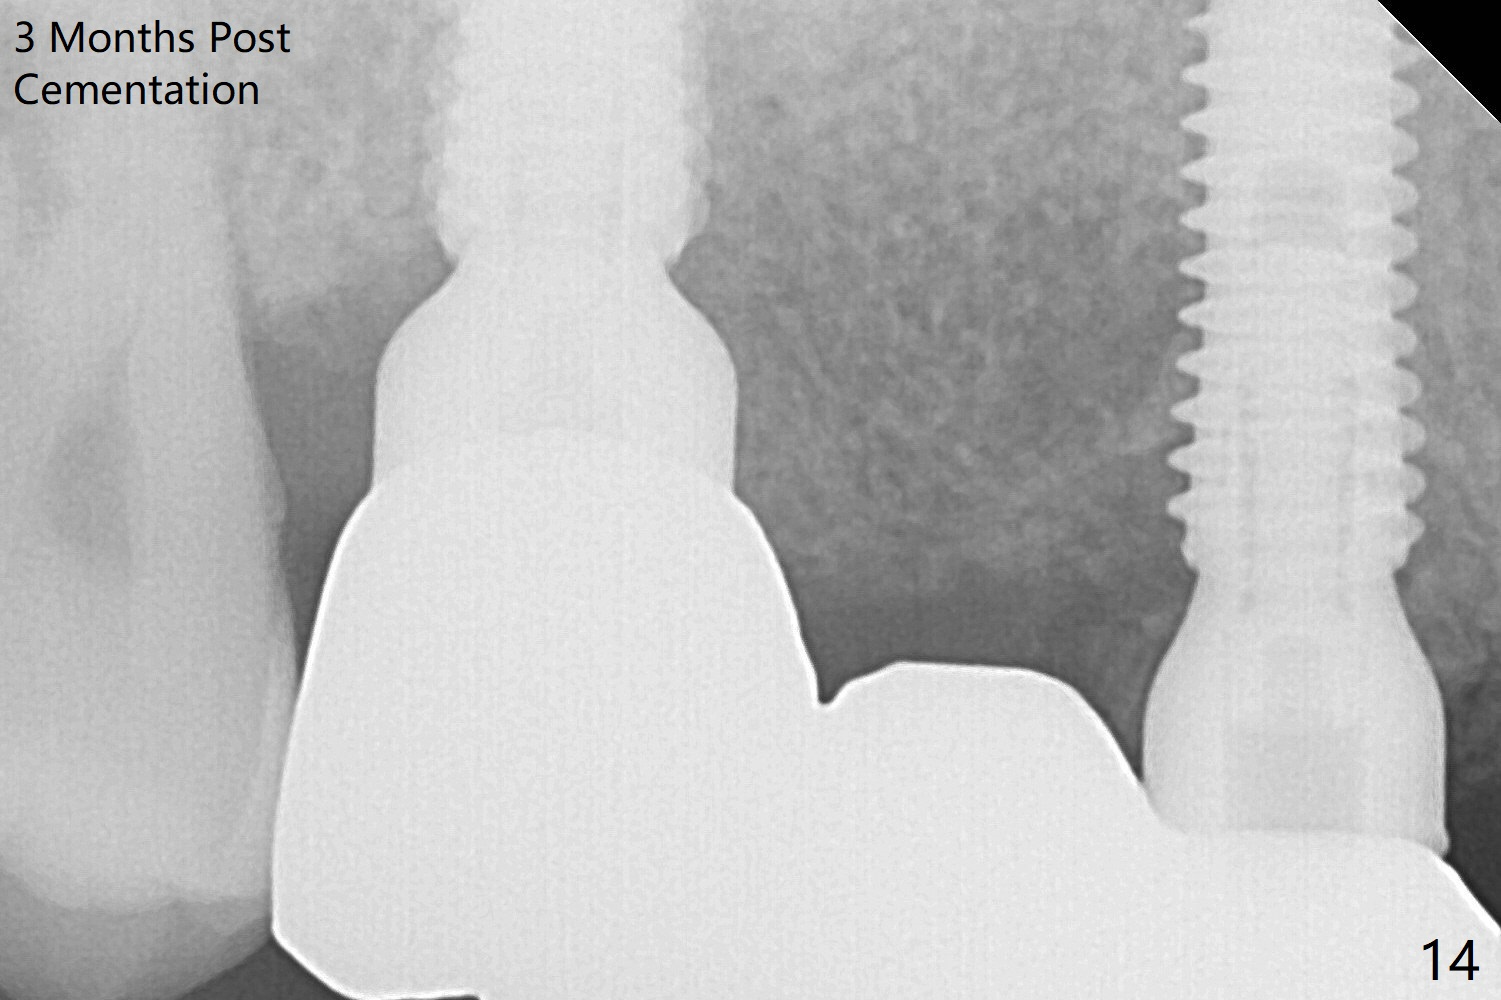

The implant at #5 is seated ~1 mm deeper (subcrestal mesially (^^); supracrestal distally (^)); allograft is placed around the implants prior to insertion of 6.5x7(5) and 5.5x4(5) mm abutments; last more allograft is added (Fig.9 *, 10). There is a large space buccally at #3 and 5, since the implants are placed palatally. Osteogen plug is placed buccally prior to placement of bone graft around the implants. The implants seem to have been osteointegrated 4.5 months postop (Fig.12). The gingiva is healthy around the implants without bone loss 3 months post cementation (Fig.13,14).